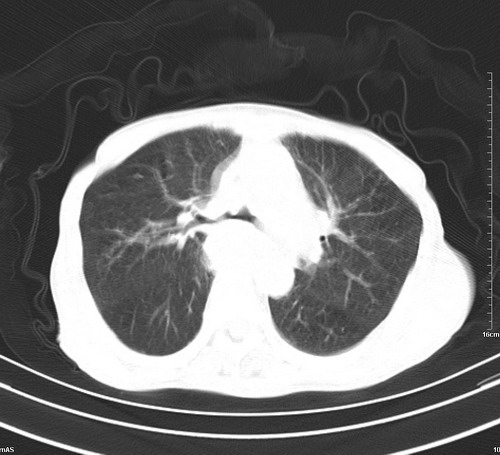

病人,女,79岁,主要因腹疼二月入院,彩超,肝,胆,脾,未见异常,胸透上消化道造影未见异常,化验白细胞增高,内科医生让做胸部ct检查,因为熟人多做了腹部(外科会诊考虑胆囊炎).现ct片如下请假各位战友.

肺癌,纵隔淋巴结转移,肝左叶病变考虑为转移病灶。

后中纵隔团块影,伴气管、食道受压移位,首先考虑转移瘤,肝s5段低密度灶。建议增强检查,另外其结肠是否有问题请提供,右肺部分肺叶局限含气增多,考虑局限肺气肿。

后中纵隔团块影,伴气管、食道受压移位,首先考虑转移瘤,肝表现同11773。

后中纵隔淋巴结肿大,首先考虑转移瘤。